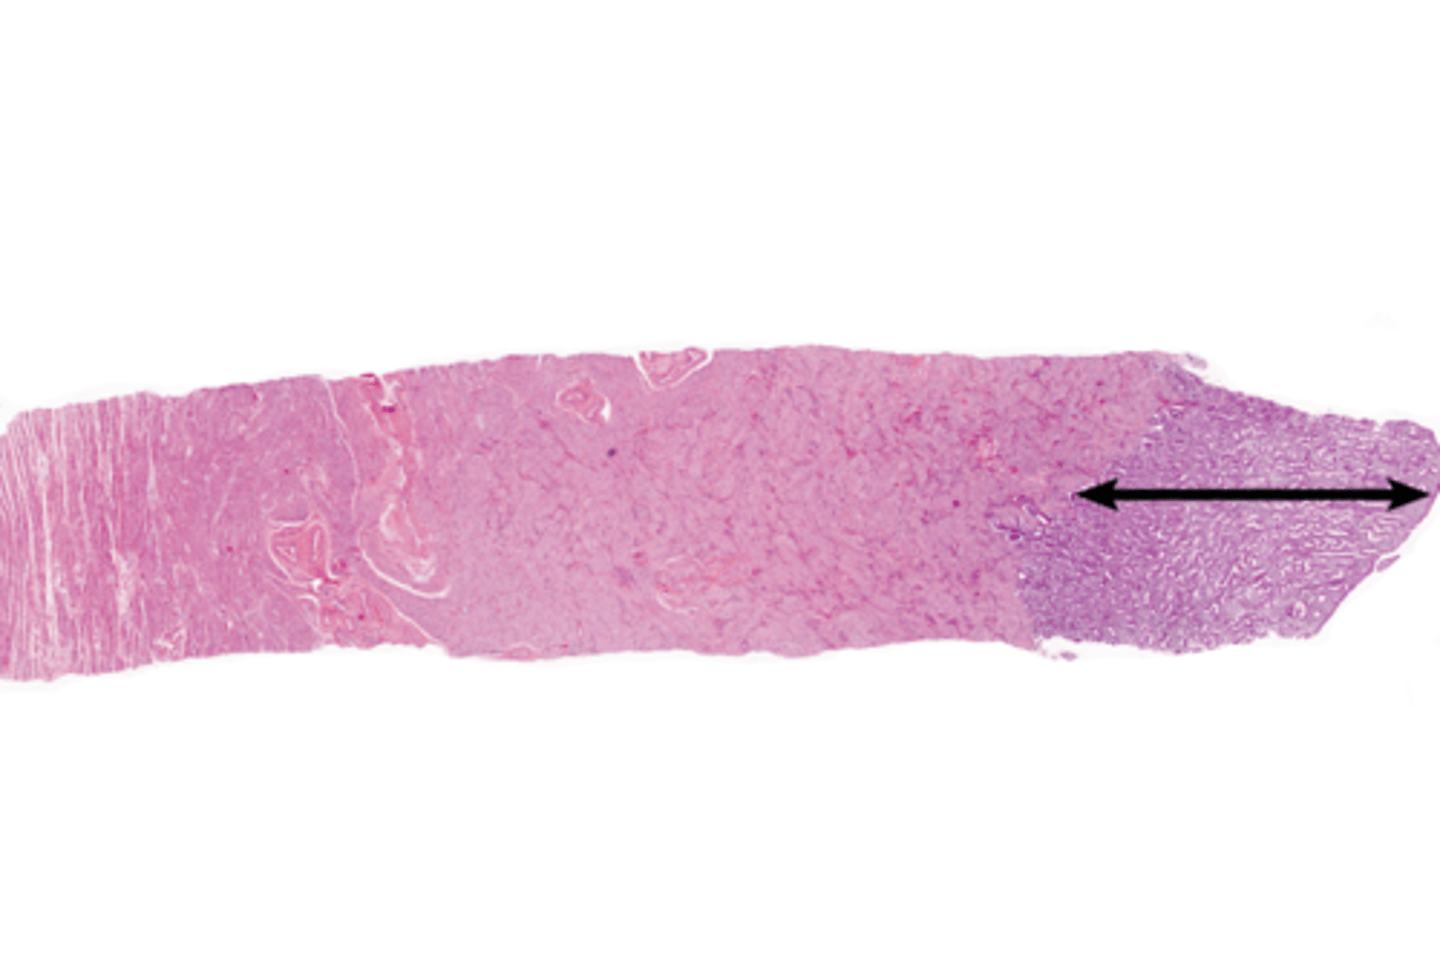

Vagina

Hymen

Vaginal fornix